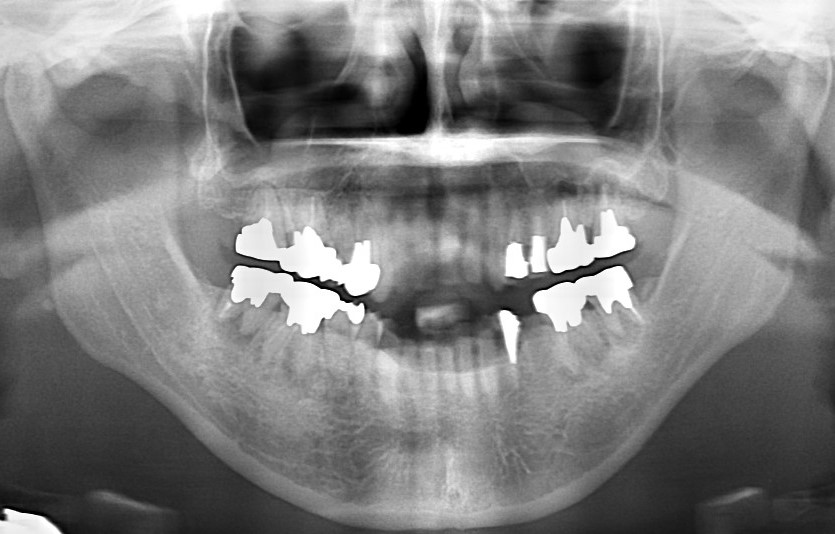

治療前 治療後

全顎的治療(インプラント+矯正)

臼歯部の根尖病巣と咬合状態の不整があり、全体的な治療を希望。   歯根破折や以前の根管治療時の穿孔などにより、保存不可能な臼歯部を抜歯。   事前にシミュレーションしておいた矯正治療後の歯の並びをもとに、適切な位置にインプラント埋入。   …